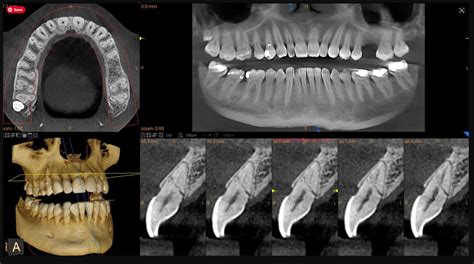

Tomografía Computarizada de Haz Cónico (CBCT)

La tomografía computarizada de haz cónico (CBCT) es una herramienta revolucionaria en el campo de la endodoncia, especialmente cuando se trata de detectar infecciones dentales y planificar tratamientos de conducto.

Beneficios de la CBCT en endodoncia:

- Permite un diagnóstico claro y preciso de conductos accesorios, reabsorciones, fracturas radiculares, poder ver la extensión calcificaciones, así como observar la proximidad de estructuras vitales.

- Está radiografía en tres dimensiones también permite valorar un traumatismo dentoalveolar (fracturas, luxaciones, desplazamientos dentales o ver el estado del proceso alveolar).

- Permite poder determinar la posible causa de un fracaso de la endodoncia, por ejemplo, pequeñas lesiones periapicales, si existen reabsorciones radiculares o fracturas de la raíz.

- Planificación precisa del tratamiento.

- Identificación de canales radiculares adicionales.

- Evaluación de fracturas radiculares.

- Reducción de riesgos y complicaciones.